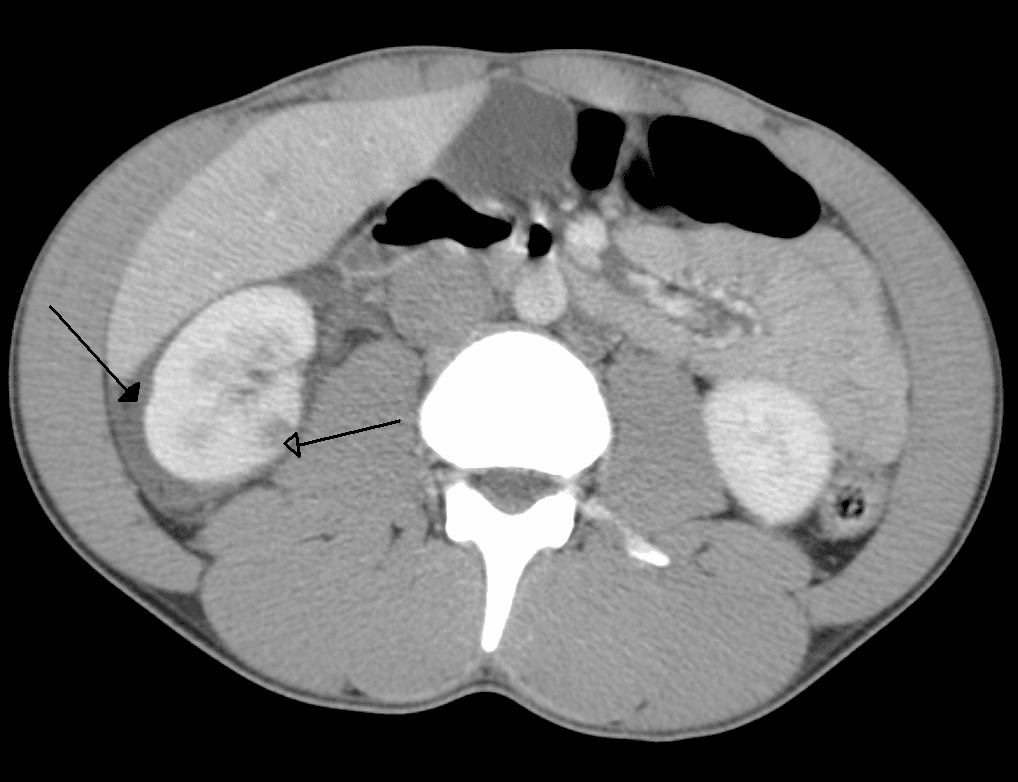

Abdominal trauma is an injury to the abdomen. Signs and symptoms include abdominal pain, tenderness, rigidity, and bruising of the external abdomen. Complications may include blood loss and infection. Diagnosis may involve ultrasonography, computed tomography, and peritoneal lavage, and treatment may involve surgery. It is divided into two types blunt or penetrating and may involve damage to the abdominal organs. Injury to the lower chest may cause splenic or liver injuries. Signs and symptoms are not seen in early days and after some days initial pain is seen. People injured in motor vehicle collisions may present with a "seat belt sign", bruising on the abdomen along the site of the lap portion of the safety belt; this sign is associated with a high rate of injury to the abdominal organs. Seatbelts may also cause abrasions and hematomas; up to 30 percent of people with such signs have associated internal injuries. Early indications of abdominal trauma include nausea, vomiting, blood in the urine, and fever. The injury may present with abdominal pain, tenderness, distension, or rigidity to the touch, and bowel sounds may be diminished or absent. Abdominal guarding is a tensing of the abdominal wall muscles to guard inflamed organs within the abdomen. Pneumoperitoneum, air or gas in the abdominal cavity, may be an indication of rupture of a hollow organ. In penetrating injuries, an evisceration (protrusion of internal organs out of a wound) may be present. Injuries associated with intra-abdominal trauma include rib fractures, vertebral fractures, pelvic fractures, and injuries to the abdominal wall. Motor vehicle collisions are a common source of blunt abdominal trauma. Seat belts reduce the incidence of injuries such as head injury and chest injury, but present a threat to such abdominal organs as the pancreas and the intestines, which may be displaced or compressed against the spinal column. Children are especially vulnerable to abdominal injury from seat belts, because they have softer abdominal regions and seat belts were not designed to fit them.